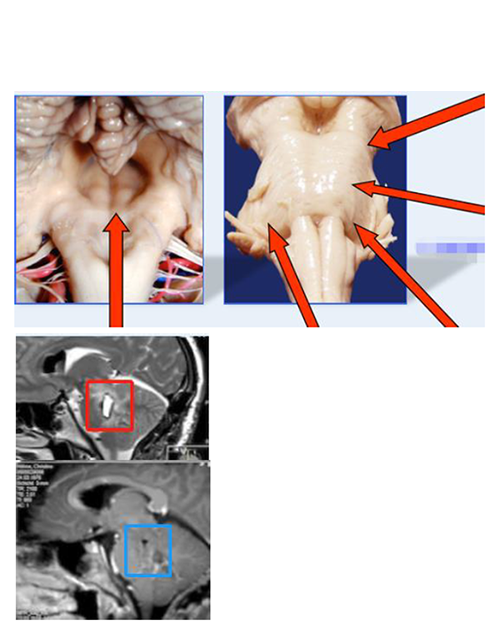

一名有高血压史的62岁女性由于意识突然紊乱而被送往另一家医院。CT扫描显示存在原发脑桥出血。她接受了2周的保守治疗。然而,她的症状没有好转,她被转到德国INI医院。入院时,她表现出意识障碍(GCS评分,13),左侧偏瘫(MMT评分,3),右侧神经III麻痹,左侧面神经(神经VII)麻痹(HB级2)。发病后21天,她通过半枕外侧入路进行手术。患者的意识水平,运动功能,眼球运动和面神经麻痹在术后早期开始好转。术后MRI显示完全切除脑桥血肿。她恢复后神志清,并且独自步行出院。

由于突然意识丧失和构音障碍,一名71岁男子被送往德国INI治疗。入院时,他表现出意识障碍(GCS评分,13),右侧偏瘫(MMT评分,3),左侧神经III和神经VI麻痹,左侧VII麻痹(HB级2)。CT扫描显示存在原发脑桥出血(下图,左起二个)。在发病后6天,在家人提供书面知情同意书后,他通过跨半长位置的半长方位进行手术。血管通过菱形窝从面部三角区撤离.尽管他的眼球运动仍然受损,但他的意识水平,运动功能和面部麻痹在术后早期开始好转。术后MRI显示完全切除脑桥血肿。